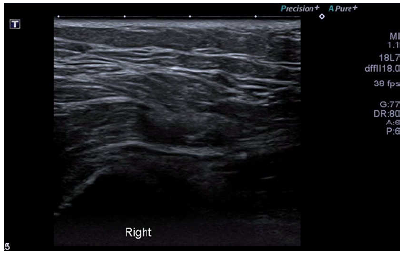

Two years after the onset of the symptoms, the patient required an arthroscopy, so a T-shaped incision of the ITB was made in the right hip using radiofrequency. During a second surgery, an X-shaped incision was made in the fasciae latae muscle on the left side, also by radiofrequency, with subsequent formation of a rhombus and fixation. The patient presented recurrence of predominant symptoms in the right hip. A control ultrasound was performed again, showing greater tendon thickening and peritendinous fluid, probably of post-surgical origin (Figure 4) (Video 2).

Ultrasound of the patient taken during post-surgical control 1 month after iliotibial band release. Persistence of symptoms. A) Increase in the thickness of the right iliotibial band (7.5 mm) with respect to the initial ultrasound. B) Dislocation of the iliotibial band during hip external rotation.

Figure 4: Ultrasound of the patient taken during post-surgical control 1 month after iliotibial band release. Persistence of symptoms. A) Increase in the thickness of the right iliotibial band (7.5 mm) with respect to the initial ultrasound. B) Dislocation of the iliotibial band during hip external rotation.

Source: Document obtained during the study.